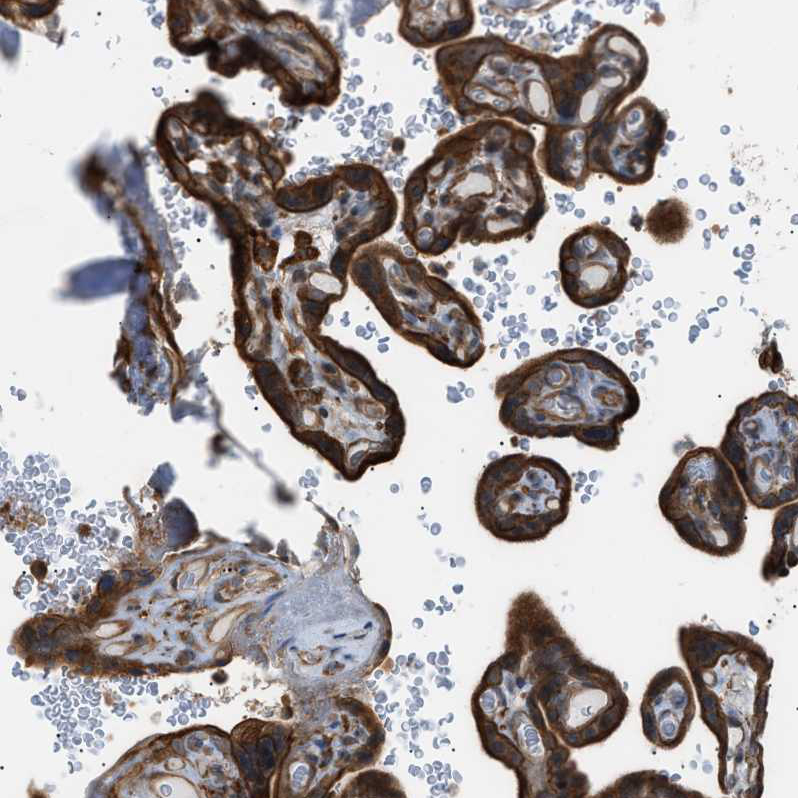

Immunohistochemical staining of human placenta shows moderate to strong cytoplasmic positivity in trophoblastic cells.